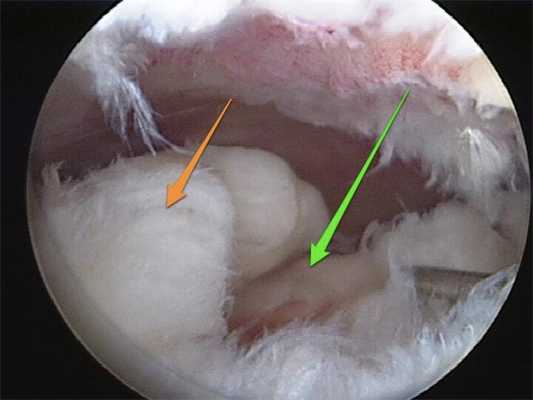

Разволокнение связок при их разрыве.

Видео в реальном времени транслируется на экране, выявляет любые существующие дефекты в больном сочленении. Если врач посчитает нужным выполнить регенерацию патологических элементов, он создаст дополнительный разрез (6-8 мм), через который нужным инструментом из микрохирургического набора устранит обнаруженный дефект. Он может сделать частичную резекцию костно-хрящевых тканей, пластику связок и сухожилий, сшивание или удаление (частичное, полное) мениска, экспроприировать хондромные тела, извлечь выпот и гной, ввести противовоспалительные лекарства, взять фрагмент тканей или синовии для изучения их состава и др.

А так выглядит пораженный сустав через артроскоп. Обратите внимание на площадь отсутствия хрящевой поверхности.